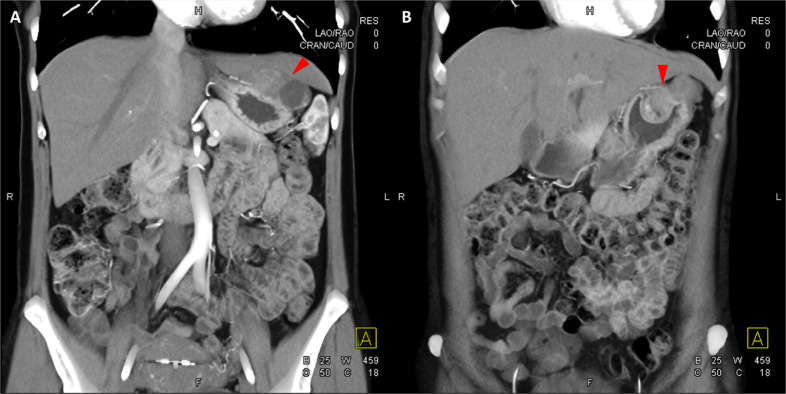

頸部增強(qiáng) CT 顯示 2 個(gè)強(qiáng)烈強(qiáng)化的腫塊。 一個(gè)位于頸部右側(cè),位于右側(cè)頸內(nèi)動脈后方的頸動脈間隙中,位于莖突內(nèi)側(cè),大小為 24 × 24 × 30 mm,頸靜脈橫向移位(圖 1A)。 第二個(gè)位于左側(cè)頸動脈間隙,在分叉處正上方展開頸外動脈和頸內(nèi)動脈,尺寸為 15 × 18 × 22 mm(圖 1B)。 影像學(xué)檢查結(jié)果與右側(cè)迷走神經(jīng)和左側(cè)頸動脈體副神經(jīng)節(jié)瘤一致,與之前的活檢結(jié)果一致。

Fig. 1

圖1:右側(cè)迷走神經(jīng)和左側(cè)頸動脈體副神經(jīng)節(jié)瘤。 (A) 軸位增強(qiáng) CT 顯示右側(cè)頸動脈間隙、右側(cè)頸內(nèi)動脈后方(白色箭頭)和莖突內(nèi)側(cè)有強(qiáng)烈強(qiáng)化的腫塊(紅色箭頭)。 (B) 軸位對比增強(qiáng) CT 顯示左頸動脈間隙有強(qiáng)烈強(qiáng)化的腫塊(紅色箭頭),向后張開頸內(nèi)動脈(紅色箭頭),向前張開頸外動脈(紅色箭頭)。 (C) 冠狀對比增強(qiáng) CT 顯示兩個(gè)增強(qiáng)腫塊(紅色箭頭)。